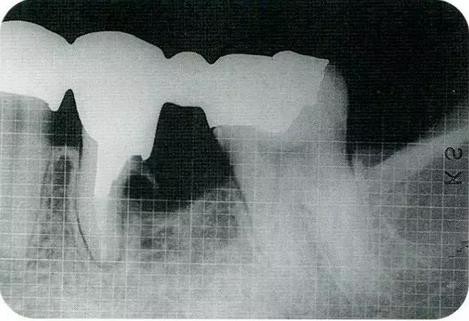

▼圖20-1

圖20-1術(shù)前X光片

▼圖20-2

圖20-2術(shù)前,左上7的牙冠明顯崩壞,齲壞已經(jīng)達(dá)到牙齦下緣深處。在進(jìn)行治療前盡可能的將軟化牙質(zhì)去除。

▼圖20-3

圖20-3將齦瓣剝離,完全去了除軟化牙質(zhì)的狀態(tài)。牙質(zhì)與骨緣處于相同的高度。

▼圖20-4

圖20-4為了得到生物學(xué)寬度,小心的使用車針沿著根面將骨質(zhì)切除。到達(dá)露出2mm健康牙質(zhì)的程度,已經(jīng)可以看到根面形態(tài)對(duì)于清掃已經(jīng)非常困難了。

▼圖20-5

圖20-5為了讓健全牙質(zhì)露出3mm,不得已將牙根分割。顎側(cè)牙根長(zhǎng)度不夠充分,所以判斷為無(wú)法保留。

▼圖20-6

圖20-6將顎側(cè)根拔除后,頰側(cè)根額側(cè)面形成了約3mm的平滑面。

▼圖20-7

圖20-7最終修復(fù)完成后。

▼圖20-8

圖20-8最終修復(fù)完成經(jīng)過了12年后。